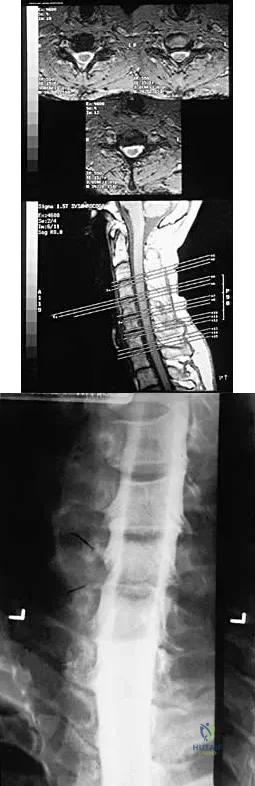

Question 22

A 32-year-old professional football player has disabling left arm pain in the C7 dermatome that has been increasing in severity for the past 2 months. Examination shows a positive Spurling test on the left side, but no changes in motor, sensory, or deep tendon reflexes. Because nonsurgical management has failed to provide relief, he has chosen surgery to allow him to complete his season. The MRI scan and myelogram shown in Figures 19a and 19b show minimal disk bulge, but a root cutoff is noted at the left C7 foramen. Electromyography demonstrates C7 nerve root irritation. Which of the following procedures will best optimize his chances for completing the season?

Explanation

Question 13High Yield

A 23-year-old man sustains a unilateral jumped facet with an isolated cervical root injury in a motor vehicle accident. Acute reduction results in some initial improvement of his motor weakness. Over the next 48 hours, examination reveals ipsilateral loss of pain and temperature sensation in his face, limbs, and trunk, as well as nystagmus, tinnitus, and diplopia. What is the most likely etiology for these changes?

Explanation

Question 14 High Yield

A 19-year-old man has had intermittent progressive knee pain with ambulation and pain at night following a rodeo accident 4 weeks ago. Figures 4a through 4e show the radiographs, a bone scan, CT scan, and T2-weighted MRI scan. What is the most likely diagnosis?

Detailed Explanation